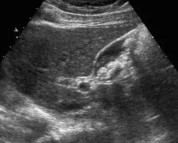

彩超显示,胆囊里确实有很多结石样的东西,但感觉发粘聚成团,而且超声能显示全貌,又不象结石一颗一颗那么硬实。

头孢曲松钙结石超声表现为泥沙样、不规则形、块状都有,但有时较粘,一般比真结石后方黑影淡,比真结石更易显示全貌。

(头孢曲松聚合物形成的胆囊假结石)